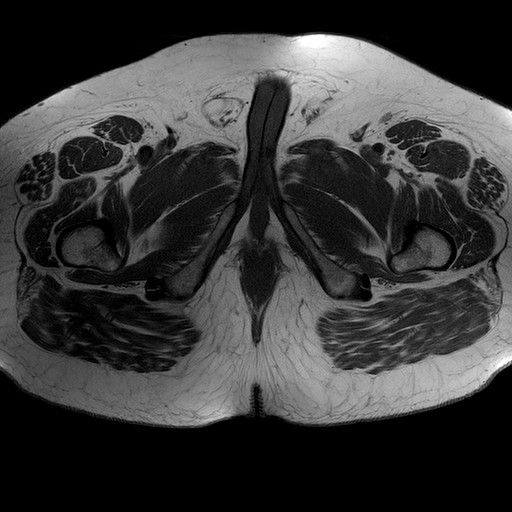

Esami: RMN BACINO

T1W_TSE

Evidenti e simmetriche alterazioni osteofitosiche in regione coxo femorale con riduzione delle rime articolari. Degenerazione completa del cercine glenoideo. Non attuali segni di versamento articolare. Non segni di edema osseo che escludono attuale algodistrofia od osteonecrosi. Lieve e simmetrica riduzione del trofismo della muscolatura glutea.